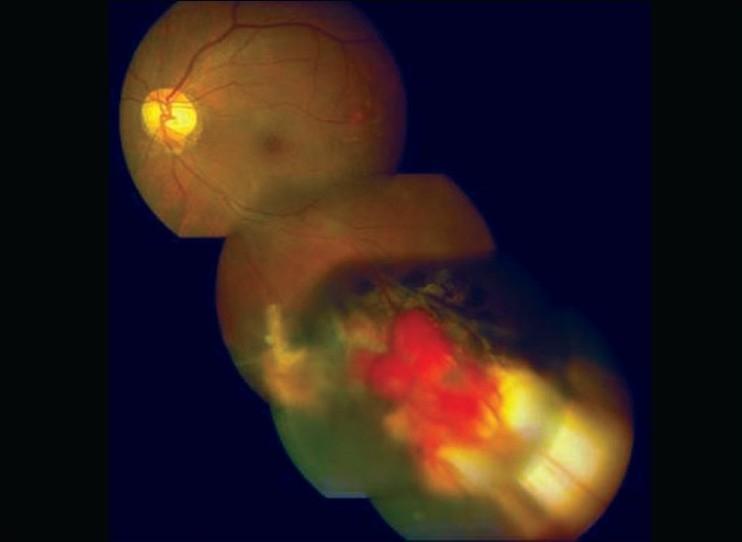

An 18-year-old boy presented to us with bilateral retinal hemangioblastoma and von Hippel-Lindau disease with history of cerebral capillary hemangioblastoma and embryonic cell carcinoma of left testes. The vision in the right eye was already lost with development of secondary closed angle glaucoma, optic atrophy with subsequent development of bullous keratopathy. The multiple retinal angiomatous lesions in the seeing left eye were treated with various modalities like triple freeze thaw cryopexy, focal lasers and transpupillary thermo therapy in multiple sittings over a period of almost 20 years since detection. One particular angiomatous lesion in the left eye was showing resistance to all the above mentioned modalities and was finally successfully treated with verteporfin and photodynamic therapy to achieve complete regression without any post-treatment complication and with a sustained 20/20 vision till a follow-up of 15 months.

一位 18 岁男孩因双眼视网膜血管瘤和 von Hippel-Lindau 病就诊,他曾患有脑毛细血管血管瘤和左侧睾丸胚胎细胞癌。右眼视力已经丧失,继发闭角型青光眼,视神经萎缩,随后出现大疱性角膜病变。左眼多发性视网膜血管瘤病变在过去 20 年中通过多次治疗,包括三重冷冻-解冻冷冻消融、局部激光和经瞳孔热疗等方式进行治疗。左眼的一个特定的血管瘤病变对上述所有治疗方法均有抵抗,最终成功地使用维替泊芬和光动力疗法进行治疗,达到完全消退,无任何治疗后并发症,随访 15 个月时视力持续保持 20/20。